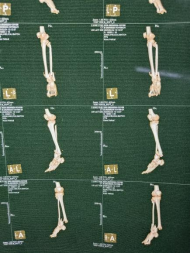

患者男性,54歲,外傷致右側(cè)脛腓骨開放性骨折8小時,局部可見右側(cè)脛骨骨折近端露出,小腿部肌肉部分損傷外露,皮膚損傷,脛神經(jīng)損傷。CT顯示右側(cè)脛腓骨遠(yuǎn)端粉碎骨折,累及關(guān)節(jié)面,骨折斷端分離移位,成角移位。